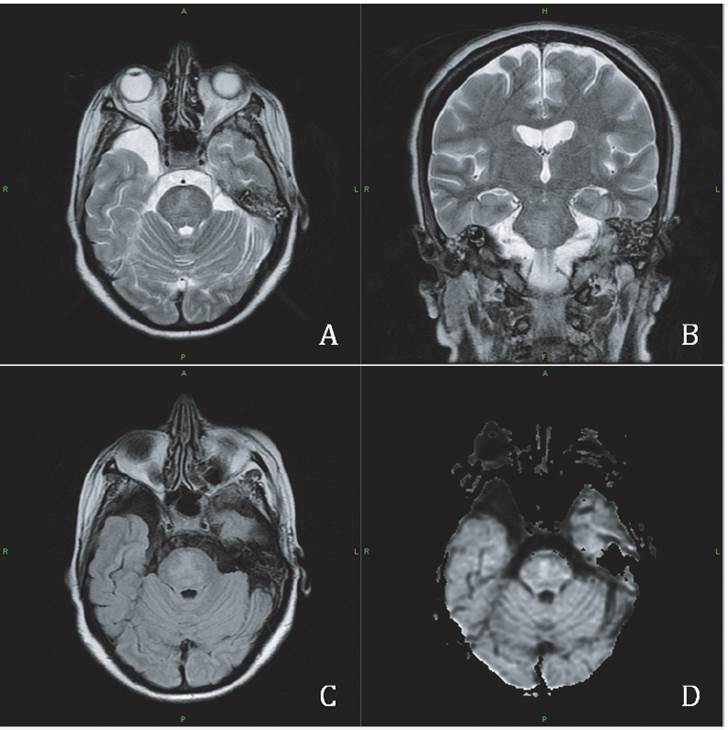

Magnetic resonance imaging showing central pontine myelinolysis. Axial and coronal T2W (A, B) and axial FLAIR (C) sequences of MR scan showing isohyperintense signal involving the central pons with hypointensity in T1W MR scan and restriction in diffusion sequences (D).

Figure 2: Magnetic resonance imaging showing central pontine myelinolysis. Axial and coronal T2W (A, B) and axial FLAIR (C) sequences of MR scan showing isohyperintense signal involving the central pons with hypointensity in T1W MR scan and restriction in diffusion sequences (D).

When the is clinical suspicion of CPM use of neuroi-maging is recommended. CT is less sensitive than MRI, but somethimes it may show a medial pontine hypodensity. MRI is the technique of choice; it shows a symmetric hypoin-tense image in the basis pontis in T1 without tegmentum or ventrolateral pons involvement, and a hyperintense image in T2, protonic density and FLAIR. Knowing that lesions appear days or even weeks after the establishment of the clinical condition is important 1,3. Diffusion imaging is ideal in early diagnosis because it shows increased signal and lesions appear earlier, (16). Head CT in this patient two days after the first neurological symptom was normal, whilst MRI, five days after CT, showed a pontine hyperintensity in T2 (Figure 2).